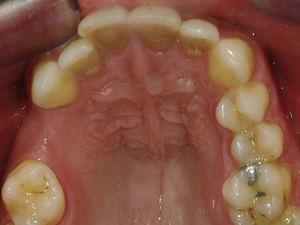

Case reportA case of a nasopalatine duct cyst in a 45-year-old male is presented (Fig. 1). The patient was referred, reporting a pressure over the anterior maxilla. There were no other symptoms and no recent history of pain. Clinical examination revealed a palatal expansion on the anterior hard palate (Fig. 2). There was no previous history of trauma. The patient was asked to take a computerized axial tomography which showed a well-defined radiolucency in the anterior maxilla in the region of incisive canal (Fig. 3). Loss of cortical bone was seen along the palatal aspect of the lesion in the sagittal sections (Fig. 4). Also resorption of nasal cavity floor bone could be seen in those sections. The cyst was enucleated under general anaesthesia. A palatal mucoperiosteal flap was raised and following bone removal, the friable, haemorrhagic cyst lining was curetted and sent for histological examination fixed in 10% neutral formalin (Figs. 5 and 6). After cyst removal it could be seen in the depth of surgical loca a small communication with the nasal cavity. Gross examination revealed a whitish, soft consistency fragment measuring 2.2cm×1.5cm×0.4cm (Fig. 7). Microscopic examination revealed fibrous wall lined by thin stratified squamous epithelium without inflammatory infiltrate and with some clear cells of ciliated appearance, which confirms the diagnosis of nasopalatine duct cyst (Fig. 8). The patient showed no clinical or radiographic signs of recurrence one year after surgical excision (Fig. 9).